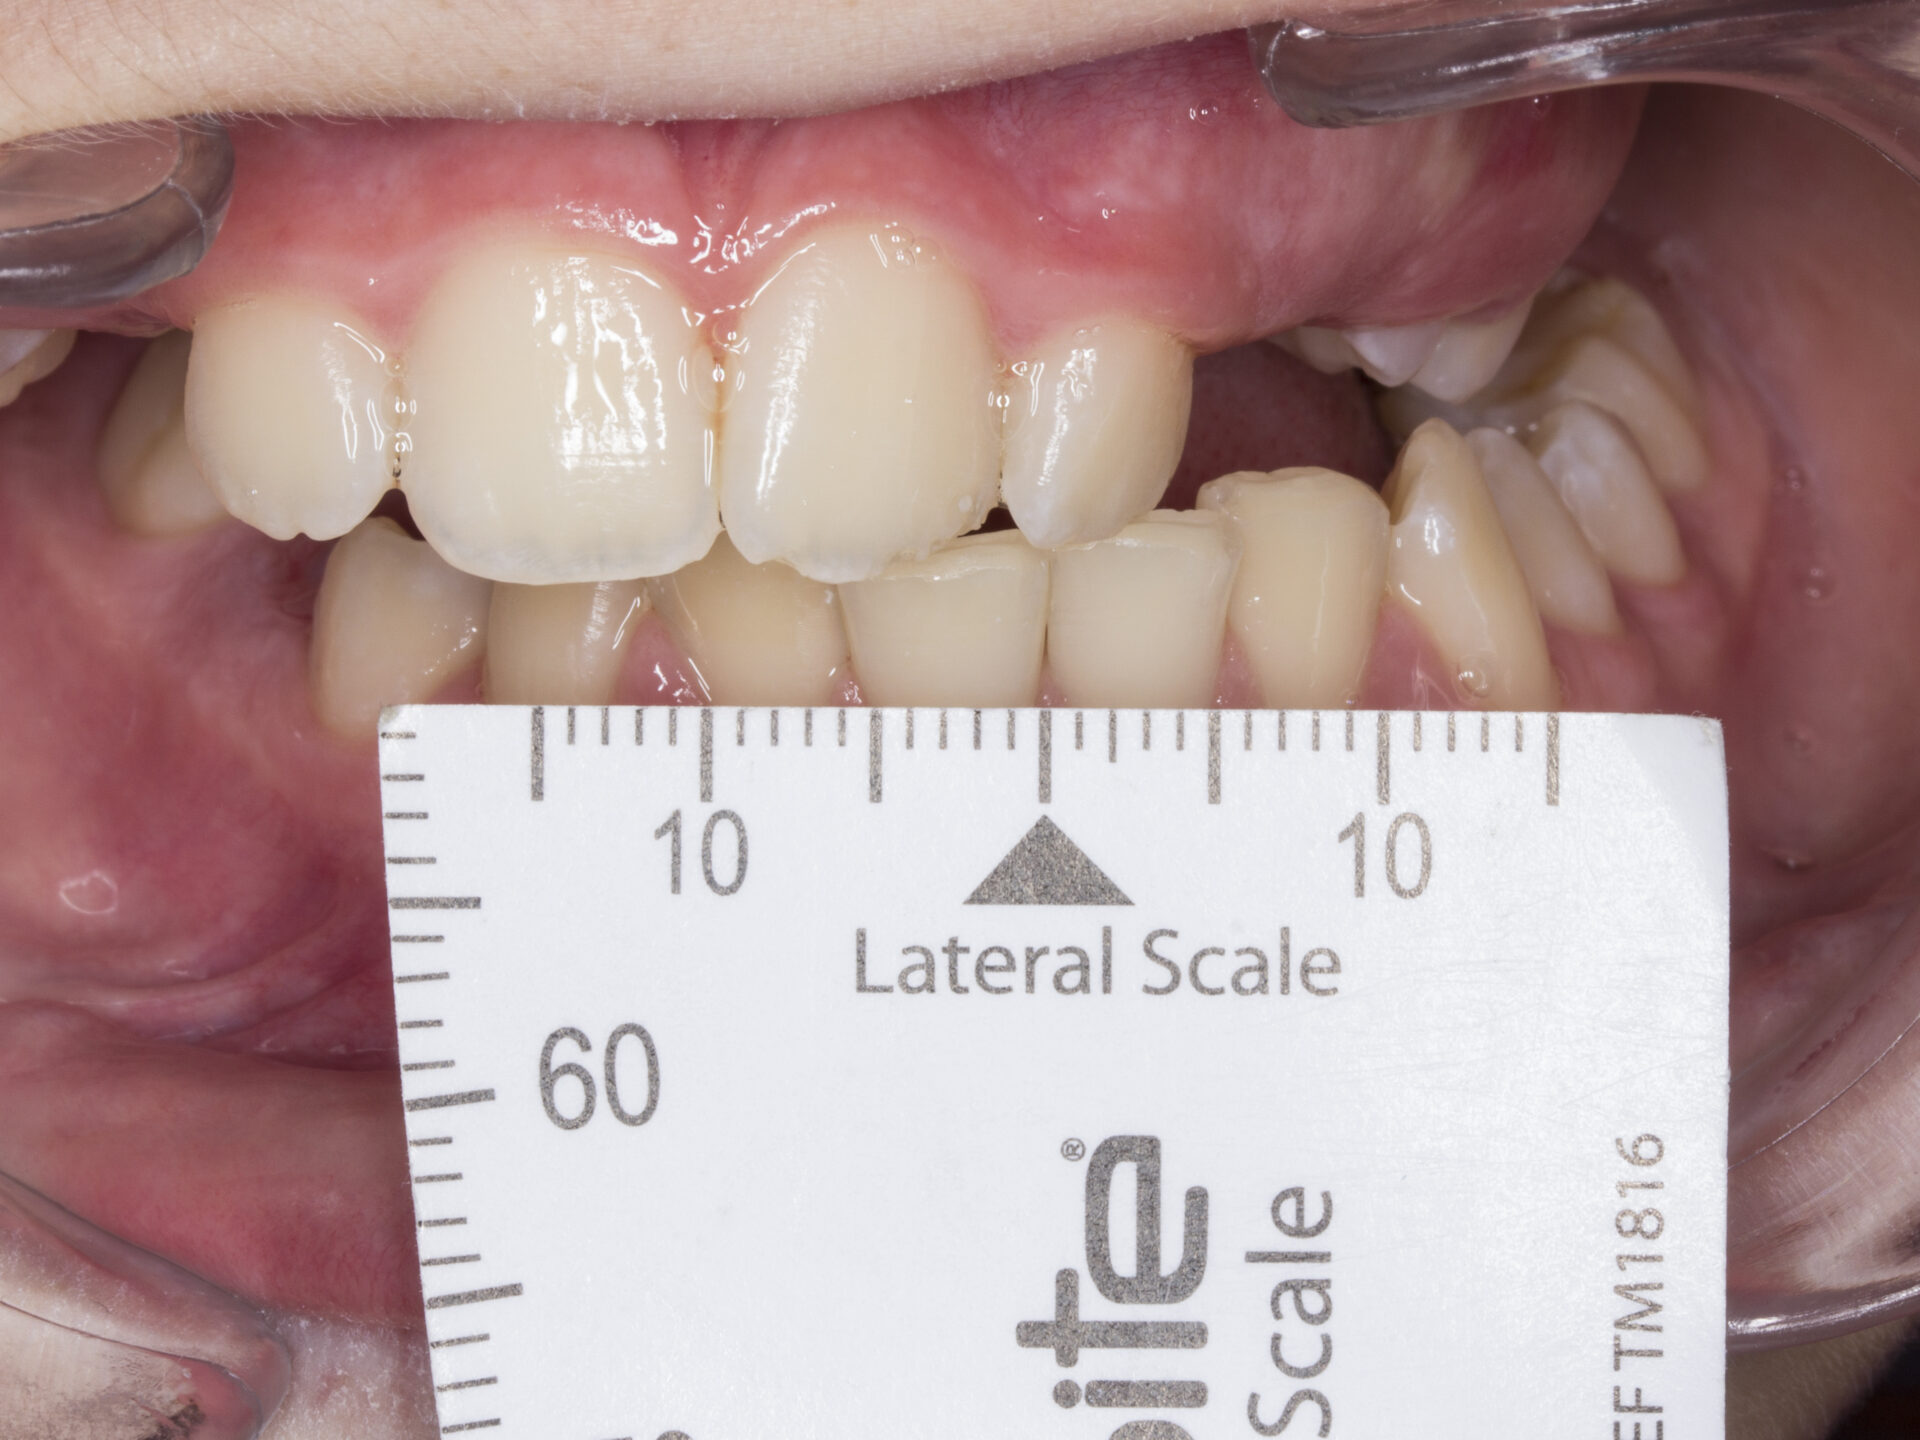

En el análisis intraoral, encontramos una Clase II molar con una mordida tijera completa del lado derecho con una pérdida de la dimensión vertical y una oclusión de los molares superiores contra la encía de la arcada inferior. Además, la paciente presenta una sobremordida de >2/3 y la imposibilidad de erupción de pieza 13, 14 y 23 por la pérdida de espacio vertical por oclusión del 33, 43 y 44. (Figuras 4, 5 y 6).

Sobremordida de > 2/3.